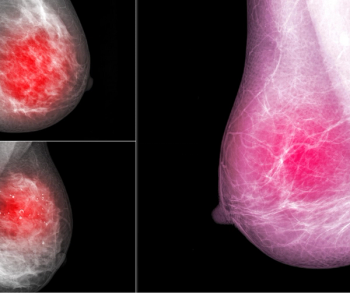

An artificial intelligence algorithm for dynamic contrast-enhanced breast MRI offered a 93.9 percent AUC for breast cancer detection, and a 92.3 percent sensitivity in BI-RADS 3 cases, according to new research presented at the Society for Breast Imaging (SBI) conference.